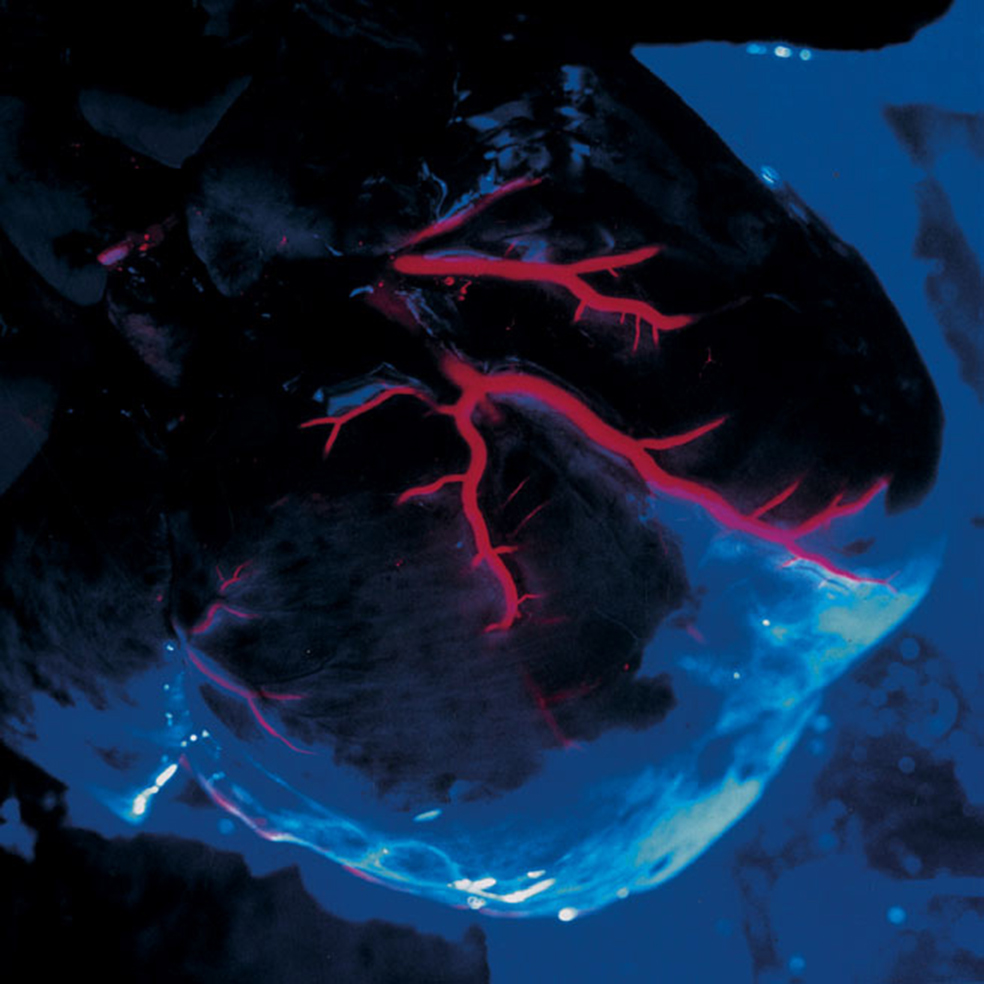

El latido

Los médicos suecos le pidieron que captara el latido de un corazón. Y dicho y hecho. Nilsson, que dedicó una gran parte de su trabajo a fotografiar órganos humanos por separado, lo logró con esta imagen casi de ciencia ficción.